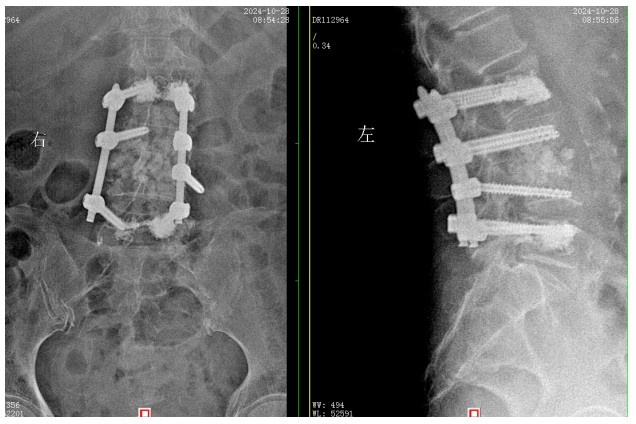

經(jīng)過積極充分的準備,錢軍博士團隊為患者成功實施了L3、L4脊柱結(jié)核病灶清除植骨融合內(nèi)固定術(shù),手術(shù)順利,術(shù)后患者腰腿痛癥狀明顯緩解,患者及家屬對治療效果非常滿意,對醫(yī)院的醫(yī)療技術(shù)以及優(yōu)質(zhì)的服務護理稱贊不已。